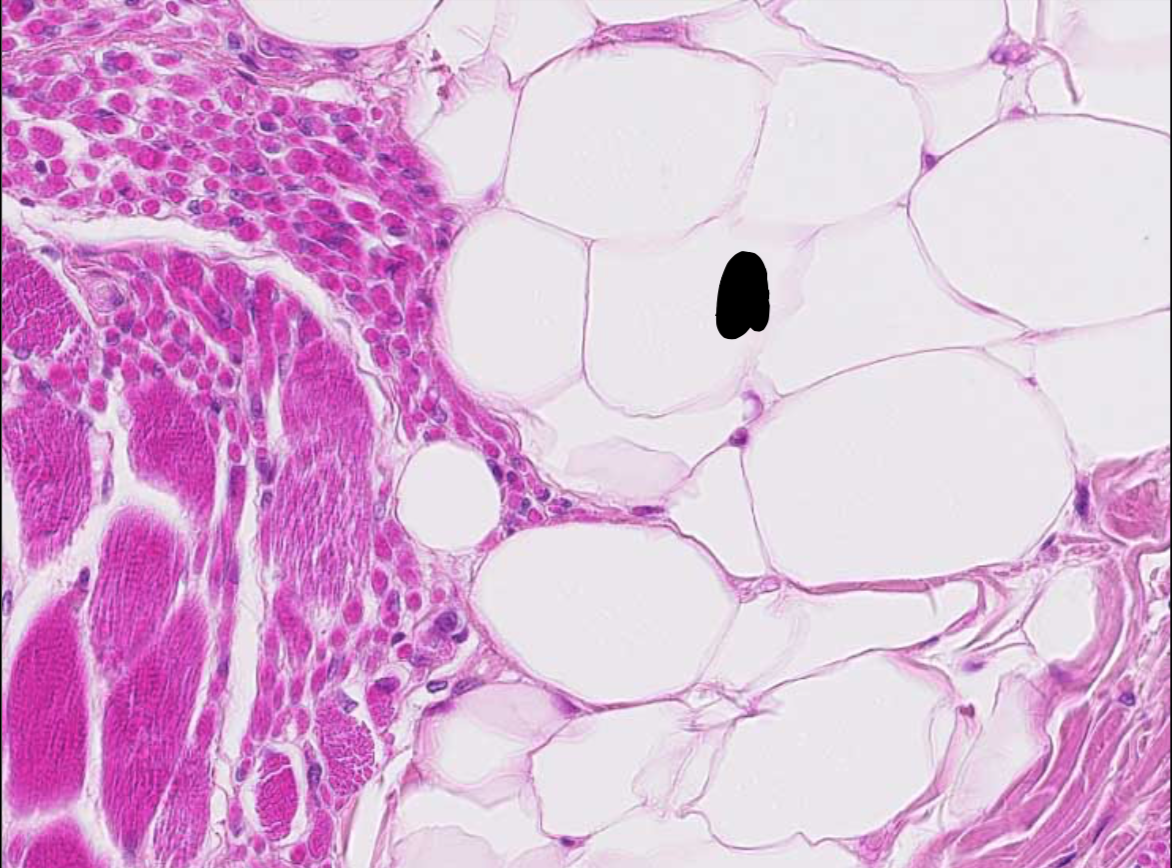

atrophie musculaire